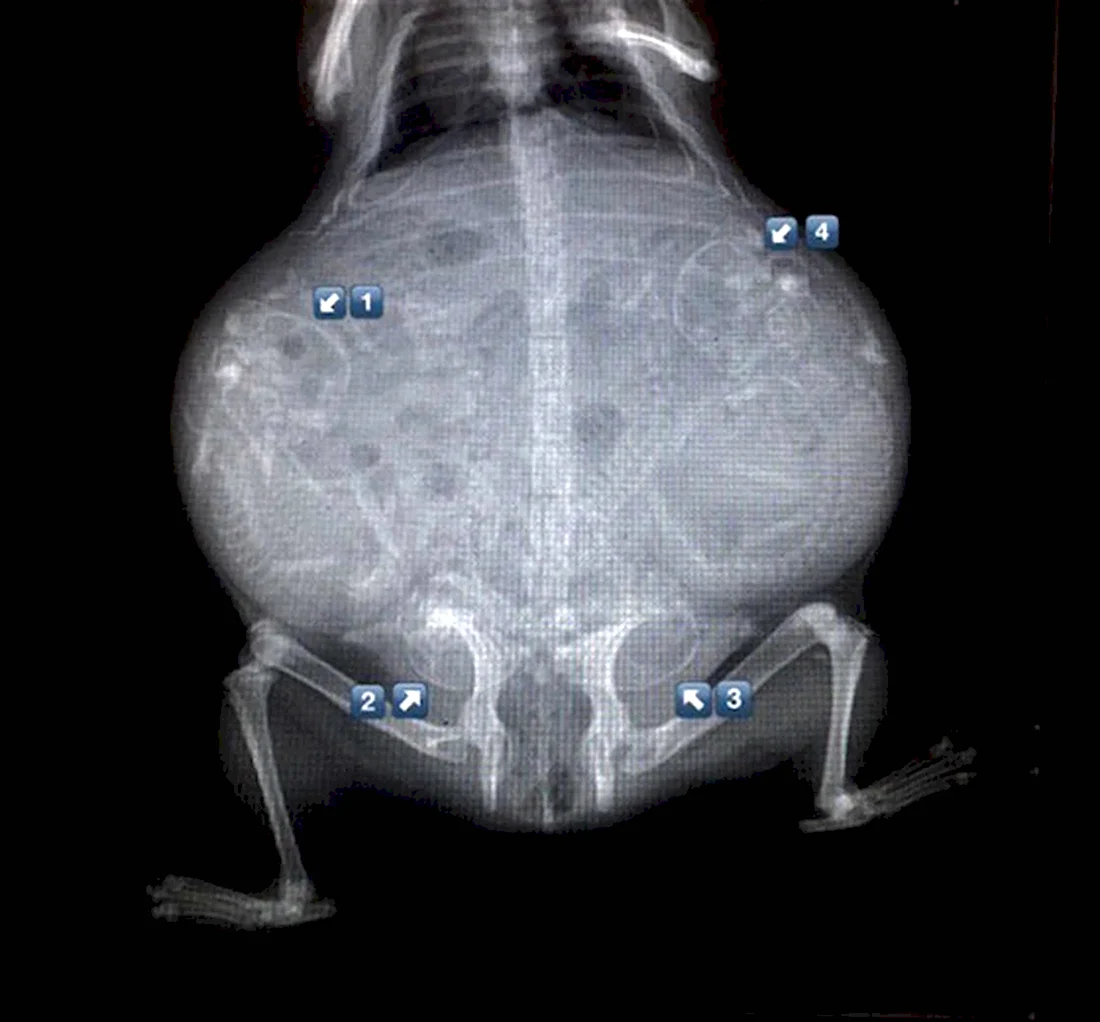

В данной статье представлена уникальная галерея фотографий, которые запечатлевают нежное чудо жизни — котят в утробе кошки. Вас ждут 35 потрясающих фото и картинок, позволяющих заглянуть в мир развивающихся маленьких созданий. Приглашаем вас окунуться в эту удивительную галерею и насладиться прекрасными видами эмбрионов кошачьих детенышей.

Так трогательно и волнующе наблюдать за процессом формирования новой жизни внутри мамы-кошки на этих удивительных фотографиях.